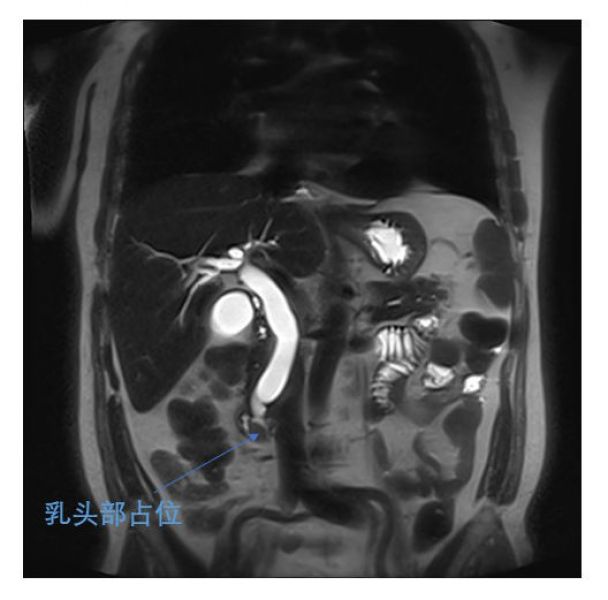

近日,肝胆一科王文儿副主任腹腔镜团队一周内连续完成两例腹腔镜下胰十二指肠切除术(LPD)。这两位手术患者均为70多岁老年男性,1人因发现皮肤巩膜黄染1月就诊发现十二指肠乳头占位,1人因纳差、乏力2月就诊发现乳头占位就诊。肝胆一科团队认真研究及评估两位患者的病情后,决定为他们实施LPD,目前两位患者术后恢复顺利。作为复杂程度很高的普外科四级手术,腹腔镜胰十二指肠切除手术在肝胆一科已作为常规手术开展。

两位患者术前MRI